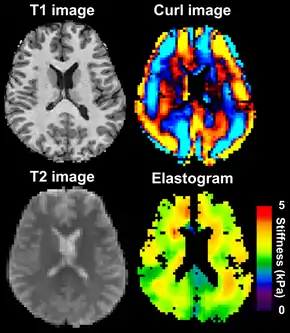

Magnetic resonance elastography of the brain. A T1 weighted anatomical image is shown in the top-left, and the corresponding T2 weighted image from the MRE data is shown in the bottom-left. The wave image used to make the elastogram is shown in the top-right, and the resulting elastogram is in the bottom-right.

MRE is conducted in three steps: first, a mechanical vibrator is used on the surface of the patient's body to generate shear waves that travel into the patient's deeper tissues; second, an MRI acquisition sequence measures the propagation and velocity of the waves; and finally this information is processed by an inversion algorithm to quantitatively infer and map tissue stiffness in 3-D.[2][3] This stiffness map is called an elastogram, and is the final output of MRE, along with conventional 3-D MRI images as shown on the right.[2]

MRE of the brain [27] was first presented in the early 2000s.[28][29] Elastogram measures have been correlated with memory tasks,[30] fitness measures,[31] and progression of various neurodegenerative conditions.[27] For example, regional and global decreases in brain viscoelasticity have been observed in Alzheimer’s disease[32][33] and multiple sclerosis.[34][35] It has been found that as the brain ages, it loses its viscoelastic integrity due to degeneration of neurons and oligodendrocytes.[36][37] A recent study looked into both the isotropic and anisotropic stiffness in brain and found a correlation between the two and with age, particularly in gray matter.[38]